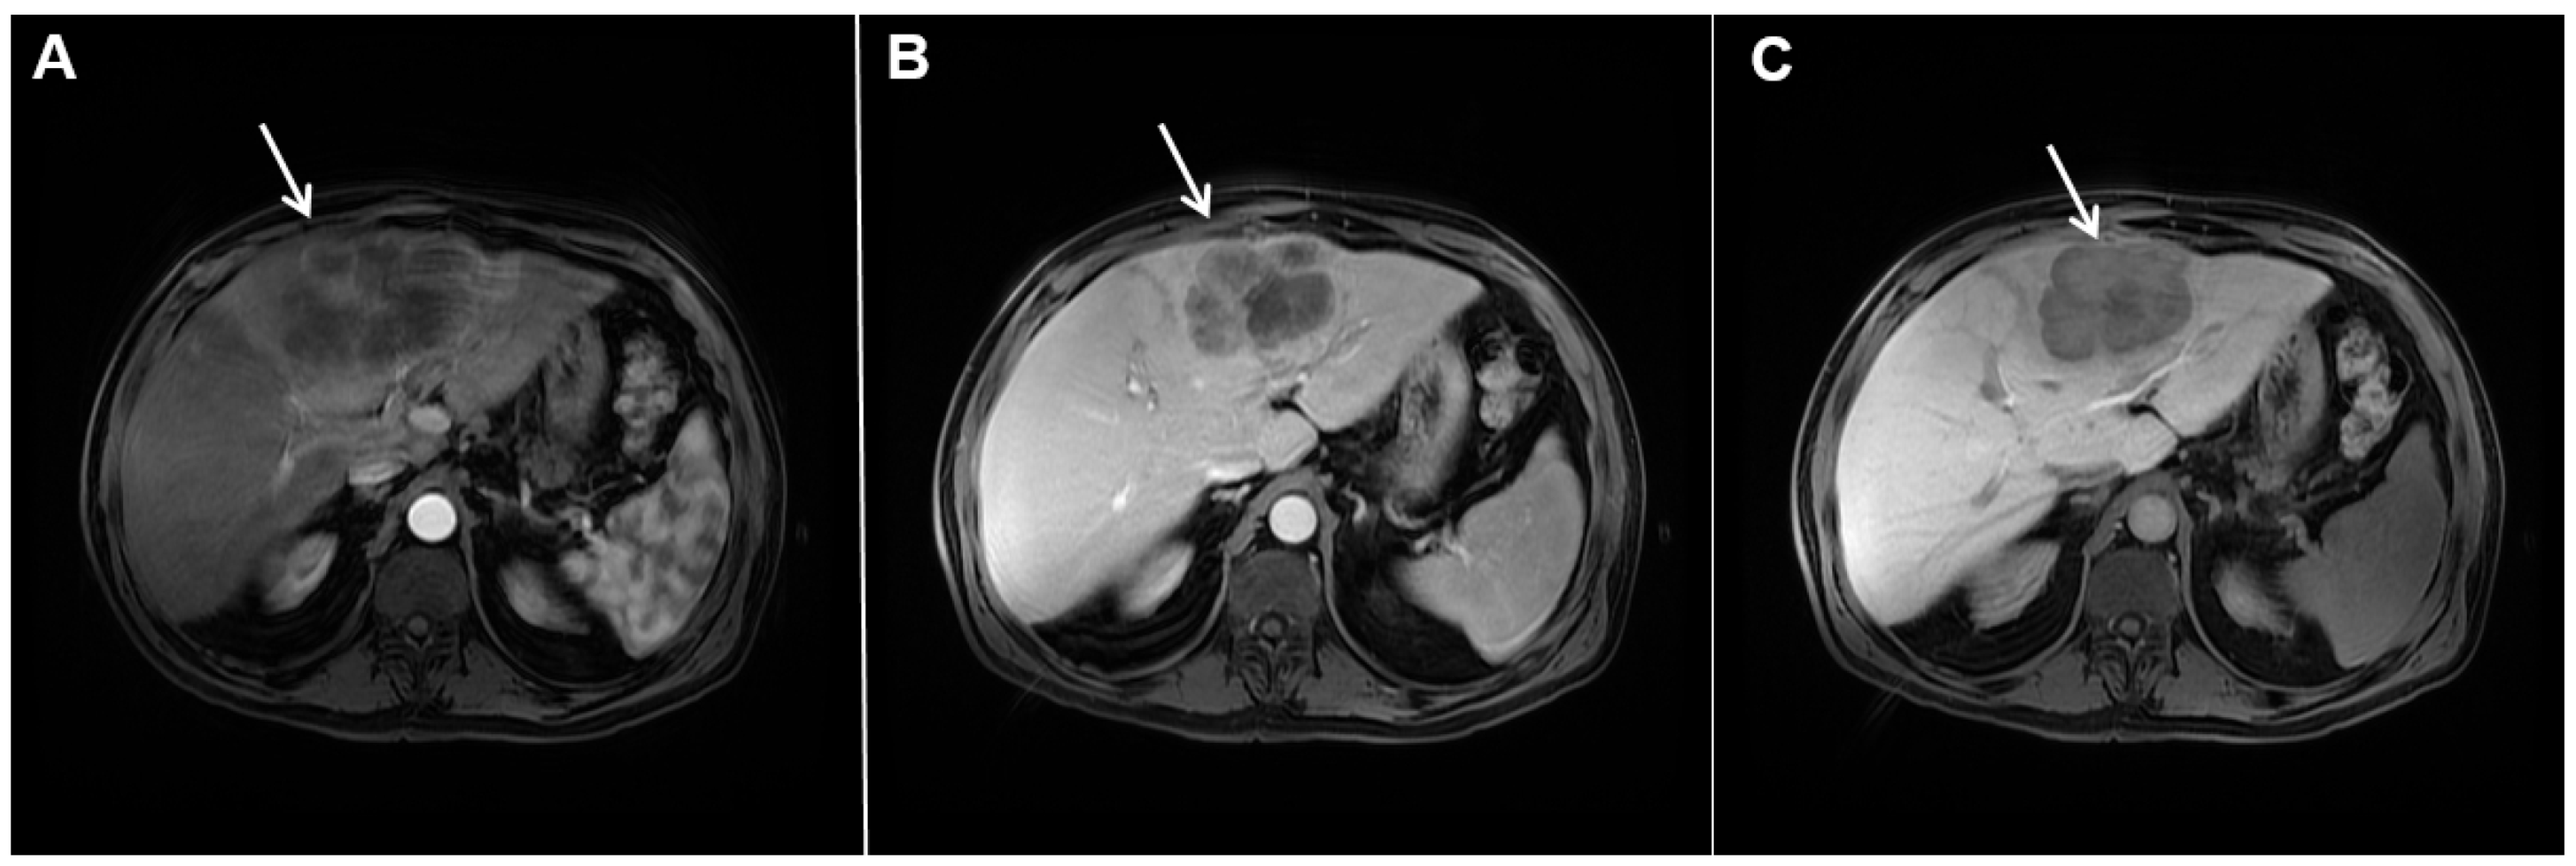

Figure 6.

Hypervascular mass-forming cholangiocarcinoma in a 63-year-old woman. The axial T2-weighted image (A) shows a moderately hyperintense tumor (arrow) located in liver segments VI and VII with a subtle medial capsular retraction. The lesion (arrow) is hypointense on the plain T1-weighted image (B), hypervascular in the arterial phase (C) with washout on the portal venous phase (D). The tumor (arrow) is hyperintense on DWI (E). Hematoxylin and eosin (H&E) staining (F) showed well-differentiated cholangiocarcinoma (arrow) surrounded by normal liver parenchyma (dashed arrow); original magnification ×40.

Mucinous cholangiocarcinoma is a rare variant of mICC characterized by rich mucin production [24,27]. According to previous studies, mucinous mICC originate from mucin-producing cholangiocytes located in large bile ducts [28]. Imaging findings in mucinous mICC reflect characteristic histopathological features of the lesion with cancer cell nests suspended in a large mucinous lake [29]. Therefore, these lesions display strong T2-weighted hyperintensity [27]. Moreover, as cancer cells in the center of the lesion are scarce, these tumors show only slight progressive enhancement of intralesional septa and cellular nests in postcontrast studies (Figure 7) [27]. Due to its very high signal intensity on T2-weighted images and centripetal pattern of enhancement, mucinous mICC may be misdiagnosed as hemangiomas [29]. Concerning similarities in the postcontrast behavior of mucinous mICC and hemangiomas, it should be kept in mind that mICC displays continuous ragged rim enhancements in contrast to the discontinuous, stronger peripheral and centripetal enhancement following the blood pool seen in hemangiomas [24,29].

Figure 7.

Mucin-rich mass-forming cholangiocarcinoma in a 78-year-old woman. The axial T2-weighted image (A) shows the lobulated hyperintense lesion (arrow) located in the subcapsular region of liver segment IVB, which is associated with capsular retraction. On the plain T1-weighted image (B) the lesion (arrow) is hypointense. In the arterial phase (C), ring enhancement can be seen with slight “ragged” central enhancement in the portal venous (D) and delayed phase (E). On DWI, diffusion restriction is noted on the periphery of the lesion (arrow) while no restriction is seen in the central part of the tumor (F). Corresponding ADC map showing targetoid appearance of the lesion is shown on (G). Hematoxylin and eosin (H&E) staining (H) showed cholangiocarcinoma (arrows) adjacent to normal liver parenchyma (dashed arrow); original magnification ×40.